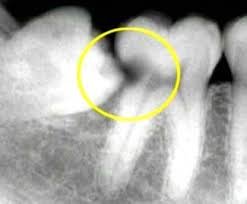

| Dental X Ray | $50 |